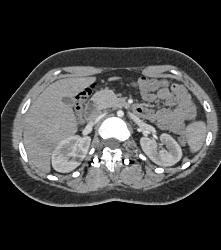

Rod in Spine for Fusion. Screws Come Very Close to Aorta